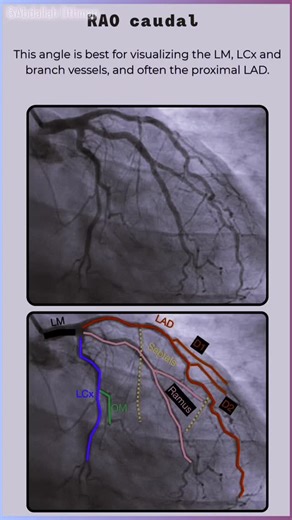

View - Coronary

Angiography - Angiographic Views

Views - Angiography